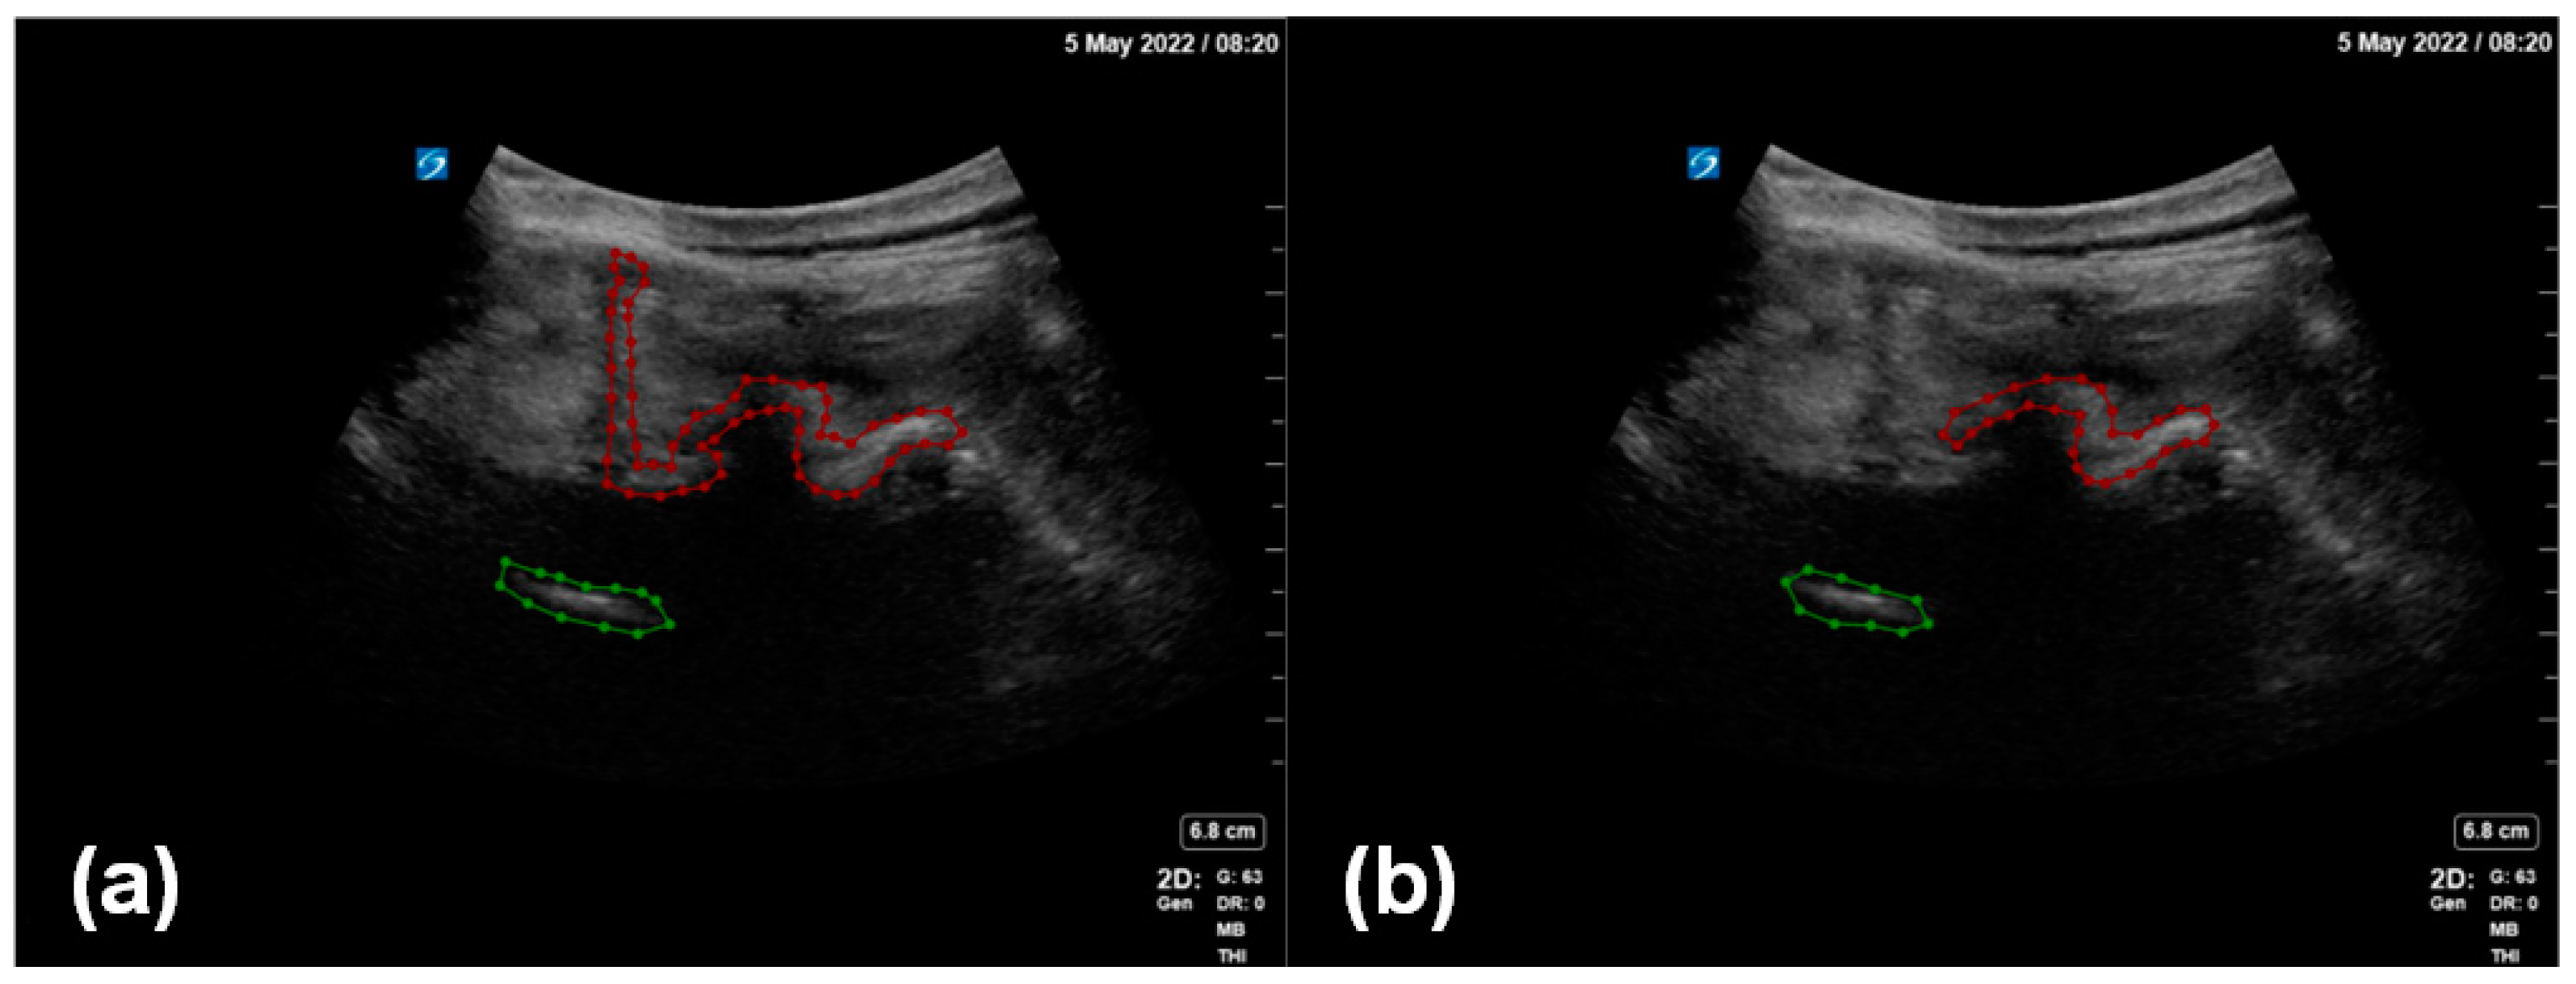

2.1.2. Enhanced Data Annotation

Two professional anesthesiologists confirmed the inclusion of a facet joint and ventral complex in all the image data and processed the ultrasound image data to remove the patient’s name, physician’s unit, and physician’s name. Under the review and proofreading of the senior anesthesiologist, the annotator marked the outline of the facet joint and the ventral complex in each image. The marking software used in this study was LabelMe (version 4.5.13), an open annotation tool. In this study, we proposed an enhanced data annotation method for the facet joint using the facet joint as the first target and the ventral complex as the second target (Figure 3). In order to evaluate the influence of data annotation on deep learning, we considered two labeling manners: (i) a local labeling method (Figure 3b), which only involved facet joints and ventral association; (ii) a full labeling method (Figure 3a), which involved transverse processes, facet joints and even bone structures in the median line and ventral association.

Figure 3. Two methods of enhanced data annotation: (a) full labeling method; (b) local labeling method. The red annotation indicates the facet joint, and the green annotation indicates the ventral complex.